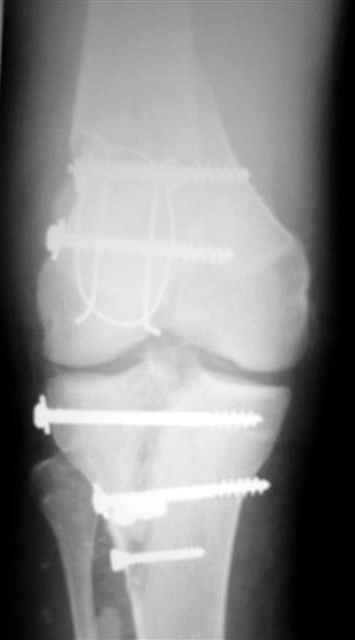

А можно,пожалуйста, более конкретно про повреждение голеностопного сустава?

В первом письме я упомянул о закрытом повреждении правого голеностопного сустава, эверсионно-пронационный механизм травмы - перелом внутренней лодыжки( поперечный, на уровне суставной щели) и отрывной перелом бугорка Chaput. После обработки открытых переломов бедра и большеберцовой кости в эту же сессию перелом внутренней лодыжки фиксировал двумя расходящимися спицами, бугорок Chaput двумя тягловыми винтами 3,5 мм. Раны заживают благополучно. Учитывая повреждение наружной группы мышц, активное разгибание в голеностопном суставе ограничено. Пассивная + пассивно-активная мобилизация голеностопного сустава с физиотерапевтом.